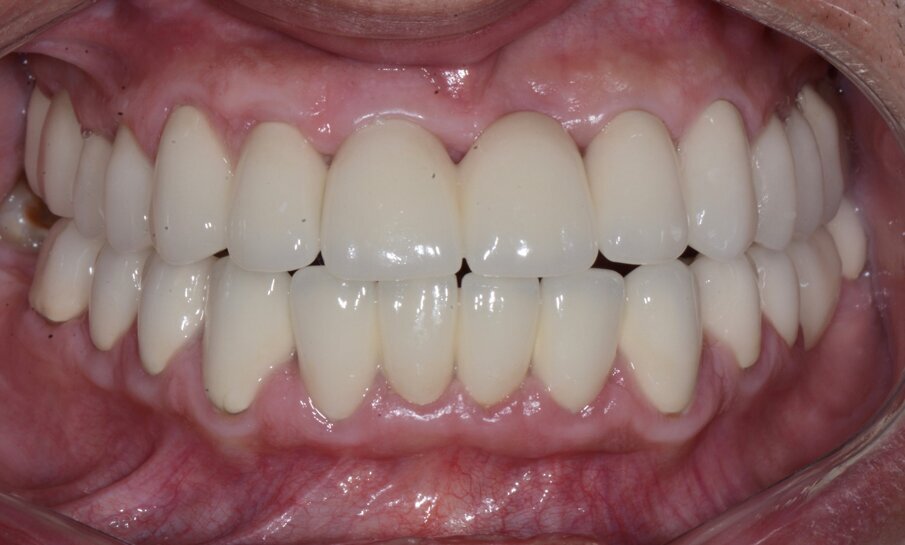

Pacijent starosti 29 godina, s agresivnom formom parodontitisa. Pacijent je u trajanju od 2 godine lečen nehirurškom, a zatim i hirurškom terapijom oboljenja parodoncijuma uz primenu preparata GelCide. Nakon 2 godine, pacijent je protetski rehabilitovan fiksnim protetskim radom.